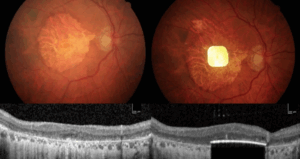

Un diminuto chip ocular inalámbrico y unas gafas de alta tecnología han permitido a 27 personas con degeneración macular asociada a la edad.